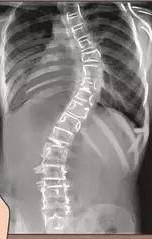

脊柱侧弯

布骨医学科普:脊柱侧弯支具佩戴,天热了怎么办?

布骨医学科普:脊柱侧弯干预和不干预的差别竟然这么大!

发现侧弯以后,积极干预还是继续观察?不同的医生给出不同的答案。有的医生擅长手术,对保守治疗并没有深入的研究,有的医生虽然不做手术,但他(她)可能对侧弯的发展有很多经验。.....

布骨医学科普:青少年特发性脊柱侧凸的病因学研究现状和进展

青少年特发性脊柱侧凸是一种在未成年人中最常见的三维脊柱畸形,发生于11~18岁之间。青少年特发性脊柱侧凸被认为是影响青少年身心健康的重要疾病,近年来,中国国内各地医疗机构开始逐步落实青少年脊柱侧凸的防治工作。若能从源头抑制或阻止青少年特发性脊柱侧凸的发生发展,则可以更有效地减少该病对未成年人的影响,.....

最新 | 中国青少年脊柱侧凸筛查临床实践指南及路径指引

青少年脊柱侧凸是发生在青少年人群中的常见脊柱疾病。青少年脊柱侧凸患者早期无明显症状,当出现脊柱畸形时往往需要手术治疗。通过早期筛查及时发现脊柱侧凸,能够有效避免疾病的进展。对青少年脊柱侧凸筛查工作进行规范非常必要。指南的制定过程参考世界卫生组织推荐的指南制定方法,由多学科专家组成指南制订小组,通过多.....

脊柱侧弯|脊柱侧弯危害大,千万不要放任它!

1.什么是脊柱侧弯?脊柱前凸、脊柱后凸、脊柱侧弯。2.脊柱侧弯有哪些危害?影响脊柱外形和功能;影响生理健康;影响心肺功能;影响胃肠系统。3.脊柱侧弯如何判断?根据脊突线判断;根据形态改变判断;根据影像学证据判断。4.脊柱侧弯如何处理? 非结构性脊柱侧凸;结构性脊柱侧凸。5.躯干肌力训练方案:膝跪位腹.....